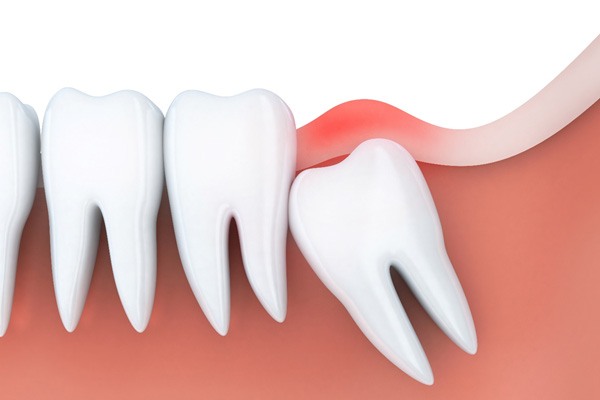

For modern humans, wisdom teeth don’t serve much of a purpose. They were more necessary for early humans when their diets were quite a bit rougher. Some people can keep their wisdom teeth, but most people don’t have enough room in their mouths, causing them to become stuck under the gumline. There are three different types of impactions:

- Soft Tissue Impaction - Your wisdom tooth erupts through your jawbone but doesn’t fully penetrate your gum, leaving the crown of your wisdom tooth either fully covered or only partially exposed.

- Partial Bony Impaction - Your wisdom tooth has partially erupted through your jawbone, but some or most of it is still stuck beneath the bone.

- Complete Bony Impaction - Your wisdom tooth is entirely submerged beneath your jawbone.

- The wisdom teeth remain completely hidden underneath the gums, meaning they’re trapped (impacted) within the jaw.

- The wisdom teeth only emerge partially through the gums.